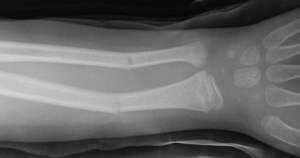

Weitere Quellen zur Wirksamkeit von Cissus Quadrangularis im Bezug auf Knochenbrüche können Sie den nachstehenden mittels Placebo kontrollierten Studien entnehmen. Sie beziehen sich Beide auf Knochenbrüche des Kiefers bzw. auf jene des Unterarmes (Speiche).